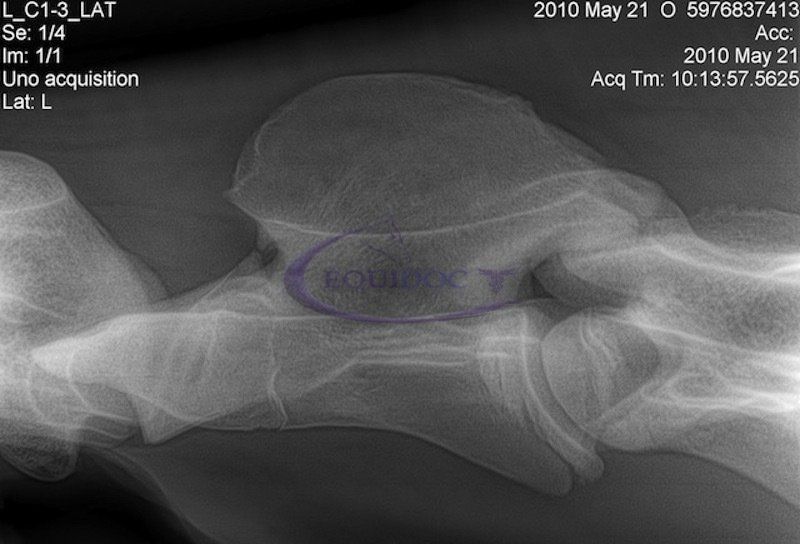

Diagnostica

La Radiologia Diretta (DR) rappresenta la più moderna tecnica radiografica digitale in alta definizione. Scopri tutti i Servizi →